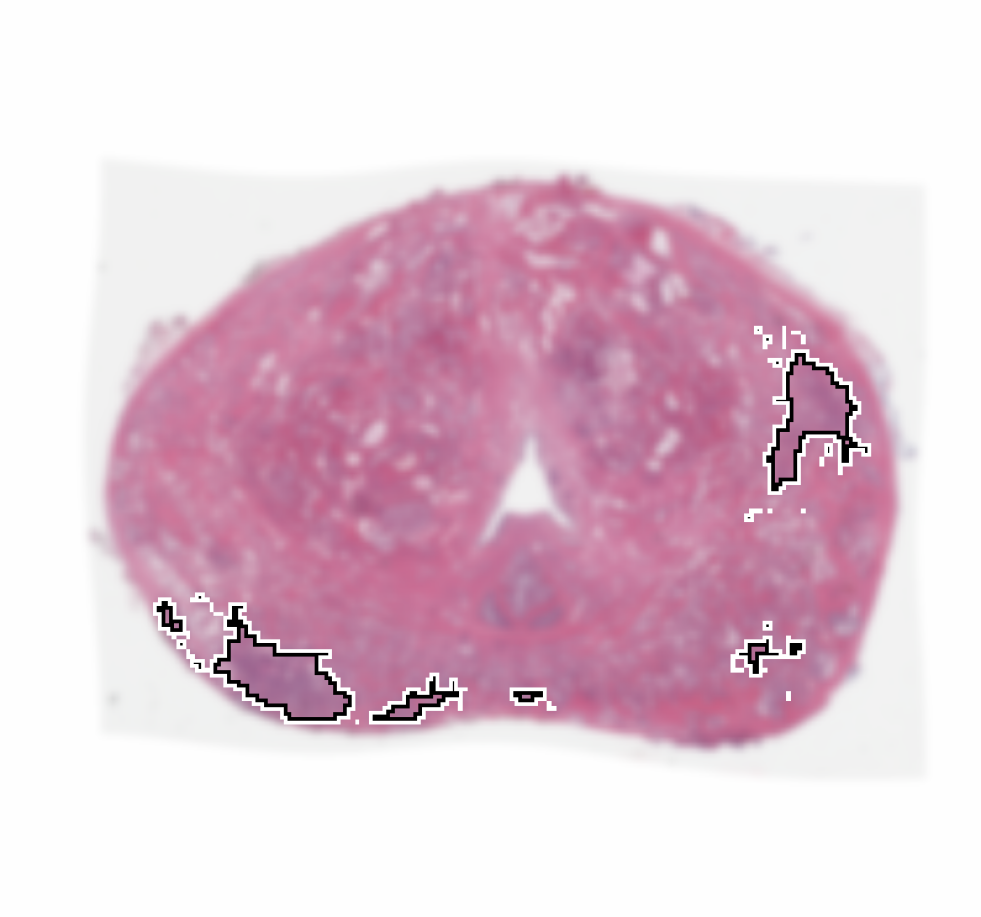

Training: From the 66 patients in the training cohort, we sampled all the cancer pixels from within the prostate, and randomly sampled an equal number of non-cancer pixels, also from within the prostate, thereby generating a training set of pixels, with equal number of cancer and non-cancer pixels. This ensured that we train the CorrNet with a balanced dataset of two classes. We used to weigh the cross-correlation error higher than the reconstruction errors. We chose a squared error loss for the reconstruction errors. We trained the CorrNet model with varying hidden layer dimensions, namely: . For each , we used a learning rate , and 300 training epochs. Figure 2 shows CorrNet representations of an example MRI slice, with .

Qualitative Evaluation: Figure 4 shows the same slice as in Figure 2 with aligned T2W, ADC, and histopathology images, and prediction results using current state-of-the-art method [4], our CorrSigNet() and CorrSigNet(T2W, ADC, ) models. It may be noted that [4] fails to detect the cancerous regions on the left and right of the images, while the CorrNet representations alone can identify the cancer regions, and when combined with T2W and ADC images, they predict the cancer regions with high probability. It may also be noted that CorrSigNet(T2W, ADC, ) shows fewer false positives than [4]. This example shows the strength of learning correlated MRI signatures in identifying subtle, and sometimes MRI-invisible cancers. Figure 5 shows more example slices from different patients, comparing the state-of-the-art approach [4] and our prediction results with CorrSigNet(T2W, ADC, ). We note that our model with correlated features (1) can identify subtle and smaller cancer regions, (2) have better overlap with ground truth cancer labels, and (3) have fewer false positives.